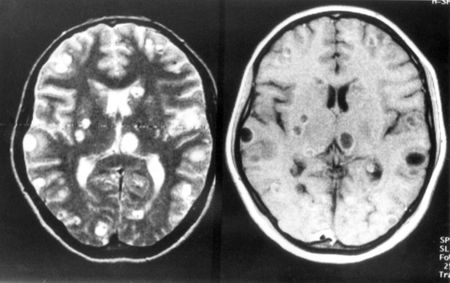

LA TENIA – Theodore Nash, impiegato nella clinica di Bethesda, nel Maryland ha avuto a che fare con persone arrivate nella sua struttura con i sintomi più disparati: chi è finito in coma, chi è rimasto paralizzato dalla vita in giù, chi non riusciva più a camminae dritto, chi aveva perso la vista, chi aveva la scatola cranica piena di liquido. Queste persone avevano nel cervello delle bolle contenenti la tenia (Taenia solium), il verme solitario. In genere questi si trovano nell’intestino ma a volte può capitare che la larva si depositi altrove, come nel cervello ad esempio, causando una malattia conosciuta con il nome di neurocisticercosi.

NEUROCISTICERCOSI – Negli Usa secondo stime non ufficiali i malati dovebbero essere circa 2000, mentre considerando la popolazione mondiale il numero cresce a dismisura. Secondo Nash “cinque milioni di casi al mondo di epilessia sono dati dalla neurocisticercosi”. A volte questa malattia viene confusa con un disordine cerebrale generico quando poi in realtà basterebbe una semplice radiografia che individui le cisti in questione.

COME ARRIVA AL CERVELLO? – Secondo una serie di esami condotti da Nash e dalla sua équipe è stato dimostrato che in America Latina le persone affette da neurocisticercosi sono comprese in una cifra compresa tra 11 e 29 milioni di persone. Ogni verme produce nel suo ciclo vitale qualcosa come 50 mila uova, custodite nelle feci dell’infettato. Ma questo accade in casi normali, ovvero quando il parassita è ancorato all’intestino. A volte però la larva può entrare nel flusso sanguigno dell’individuo finendo in posti strani come il cervello, dove si fermano e creano la cisti, che può portare alla lunga alla morte a causa dell’auomento delle sue dimensioni.